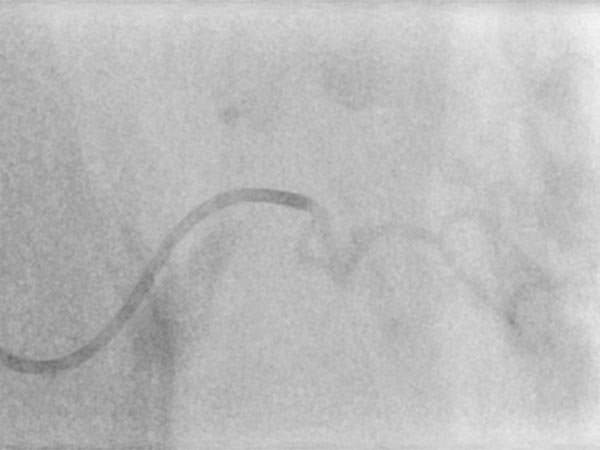

Nachdem am Ende des 3. Lebensjahres immer noch keine Rückbildungstendenz des Tumors sichtbar war, wurde nach einer Biopsie eine Embolisation zur Induktion einer Involution durchgeführt. Die Digitale Subtraktionsangiographie (DSA) zeigt einen Mikrokatheter superselektiv in einem Tumorgefäß. Der Tumor ist stark perfundiert und lobuliert, sehr früher venöser Abstrom, typisch für ein NICH.

Partikelembolisation mit sphärischen Partikeln der Größe 250 Mikrometer über den superselektiv in den Tumor eingeführten Mikrokatheter.

Weitere Tumorgefäße mit blush-artigem, diffusem Enhancement, typisch für Gefäßtumor/NICH. All diese Gefäße müssen selektiv embolisiert werden um eine Involution zu induzieren.

Weitere selektive Partikelembolisation. Die mit Kontrastmittel gemischten Embolisationspartikel verbleiben in den Tumorgefäßen.

Auch in der Übersichtsangiographie über die linke Arteria iliaca externa zeigt sich keinerlei Perfusion des Tumors mehr, die Tumorvaskularisation ist somit erfolgreich superselektiv vollständig verschlossen. Alle nicht pathologischen Arterien sind erhalten.